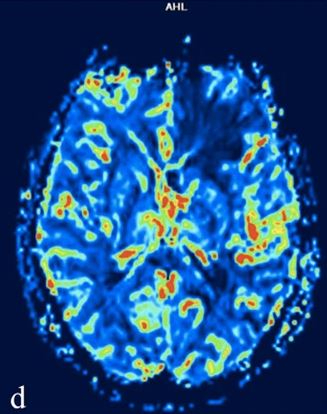

This paper illustrates the possible different radiologic patterns of radiation necrosis that can be seen through different MRI techniques in patients treated with hadrontherapy for tumors involving the skull base. The authors also present images of exemplary cases of radiation necrosis.

Article: Brain MR findings in patients treated with particle therapy for skull base tumors